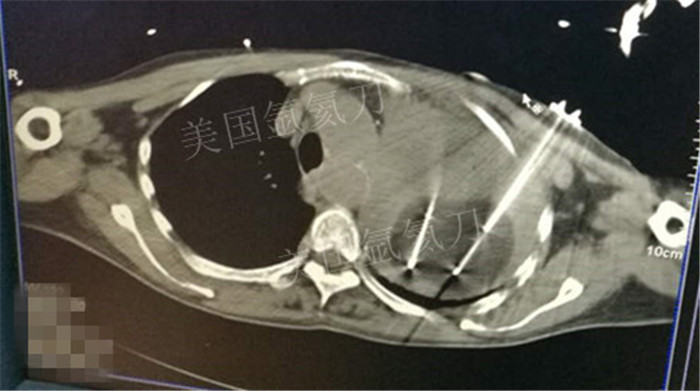

下一篇:氩氦冷冻治疗最大径8.2肿瘤,冰球最大径7.9